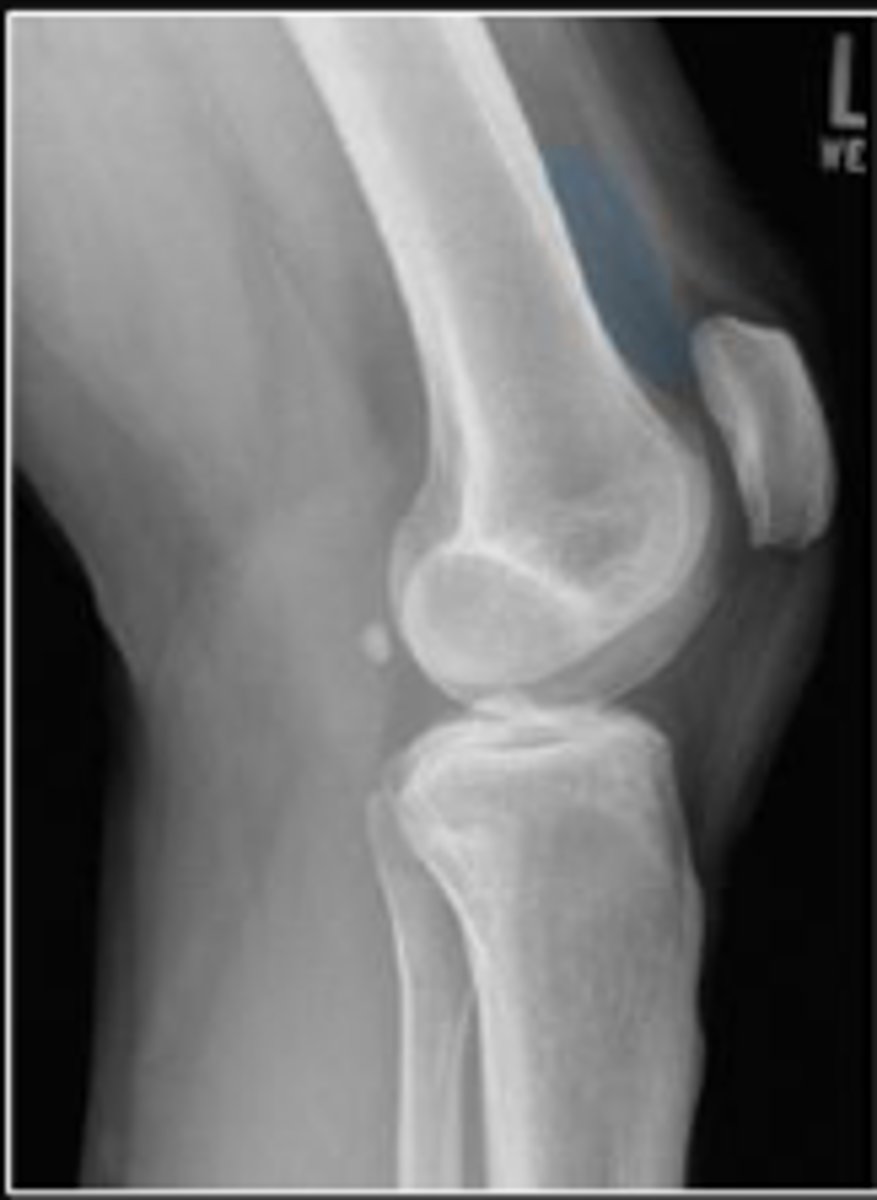

Lateral collateral ligament

What inserts at the location of the blue arrows?

Lateral collateral ligament avulsion fracture of

the right knee

What is the most significant radiographic finding?